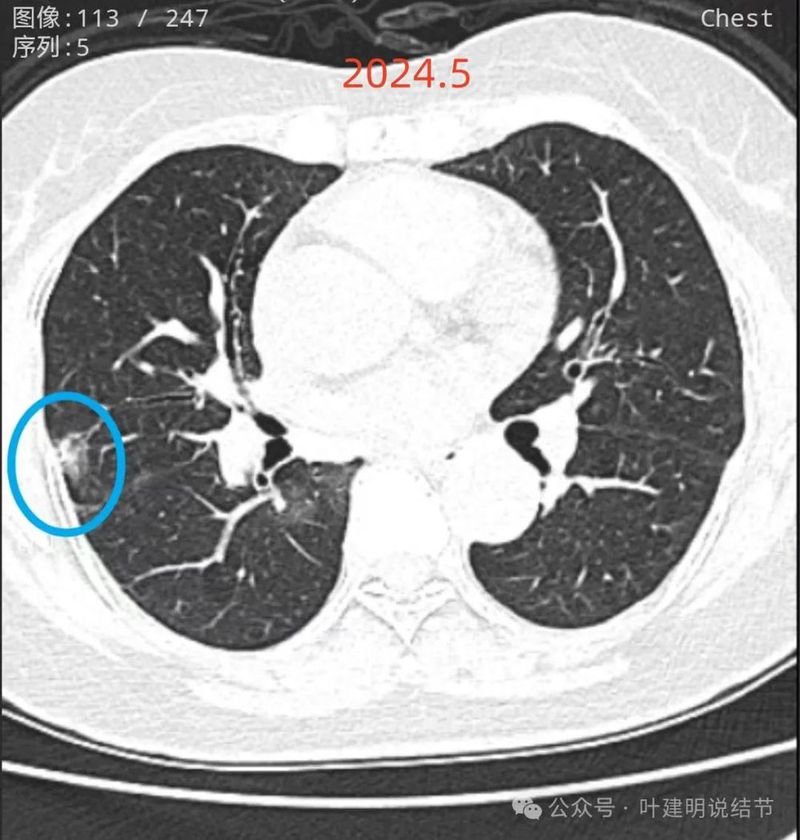

再看2024年5月时的影像:

病灶8:右中叶混合密度结节,较前实性成分增多,边缘毛刺明显起来,考虑浸润性腺癌可能性大;

两肺多发磨玻璃结节,部分是混合密度。主病灶是红色这处在左上叶的,对比2021年有明显增大进展,考虑是浸润性腺癌可能性大,或者微浸润性腺癌;粉色的考虑原位癌可能性大;橘色的考虑不典型增生可能性大;黄色的考虑肺泡上皮增生可能性大;紫色的考虑微浸润性腺癌可能性大;绿色的考虑良性的可能性大;蓝色的考虑浸润性腺癌或者微浸润性腺癌;黑色的是2021年的时候比较明显的几处病灶。总体对比来看红色的范围增大比较明显,实性成分也有增加;蓝色的密度增加比较明显。首先考虑是多原发早期肺癌。个人觉得继续随访存在一定风险,当然由于病灶太多,也不是说都靠外科手术能够解决问题的,但是主要的有风险的病灶如果能够手术还是需要手术先解决,其他次要的病灶后续再考虑消融或者其他治疗。我的想法是先做右肺下叶背段切除(紫色,考虑微浸润或浸润)加上叶楔形切除(蓝色),下叶粉色的也可楔切或不切;之后看恢复情况过三个月左右再做左肺上叶切除。其余病灶后续如果随访进展考虑消融控制。意见供参考!为何先建议做右侧:先做右侧是因为右侧切得少,到时候再切左侧的时候,单肺通气更能耐受。如果先做左侧,下次做右侧时,左下叶单肺通气不太能耐受些。而且蓝色这处密度增加明显,又贴着胸膜,它的风险相对来说也较高,或许比左上红色的还高点。所以先做右侧。若非转移,靶向药个人不太建议吃,又不是晚期,是多原发早期肺癌可能性大呀。